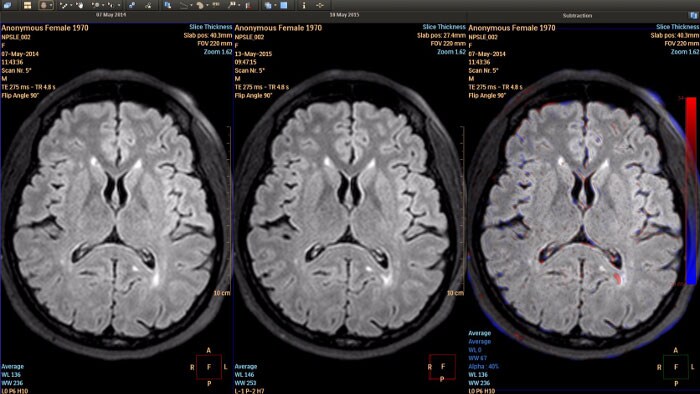

Longitudinal Brain Imaging (LoBI) por RM

Suporta a avaliação de distúrbios neurológicos controlados com exames cerebrais em série, ajudando a monitorizar o estado e a progressão da doença.